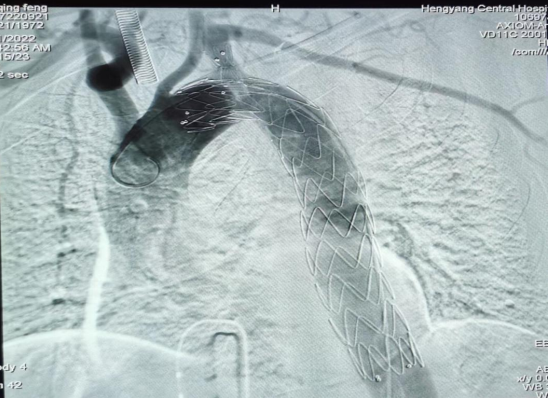

疾病的兇險(xiǎn)與手術(shù)費(fèi)的昂貴,讓許先生一家人左右為難。了解許先生經(jīng)濟(jì)困難,心血管中心趙慶禧主任醫(yī)師與患者充分溝通后,決定放棄傳統(tǒng)的穿刺方法(需使用血管縫合器),行股動(dòng)脈和左側(cè)肱動(dòng)脈切開(kāi)入路,既保證了手術(shù)安全性又兼顧了經(jīng)濟(jì)性。最終在9月21日,許先生愿意接受介入微創(chuàng)治療。趙慶禧帶領(lǐng)介入團(tuán)隊(duì)和麻醉科團(tuán)隊(duì)密切配合,為其施行全麻下行“Castor分類型覆膜支架植入術(shù)”。僅在患者的左肱動(dòng)脈,右股總動(dòng)脈處分別做不到1cm的小切口,然后在DSA引導(dǎo)下精確定位,釋放覆膜支架一枚,保住鎖骨下動(dòng)脈的同時(shí)也堵住了主動(dòng)脈內(nèi)膜破口,手術(shù)歷時(shí)三個(gè)小時(shí),順利完成,“致命炸彈”被徹底拆除,術(shù)后許先生恢復(fù)良好,于住院的第30天順利出院。

(術(shù)中釋放的一體式覆膜支架)